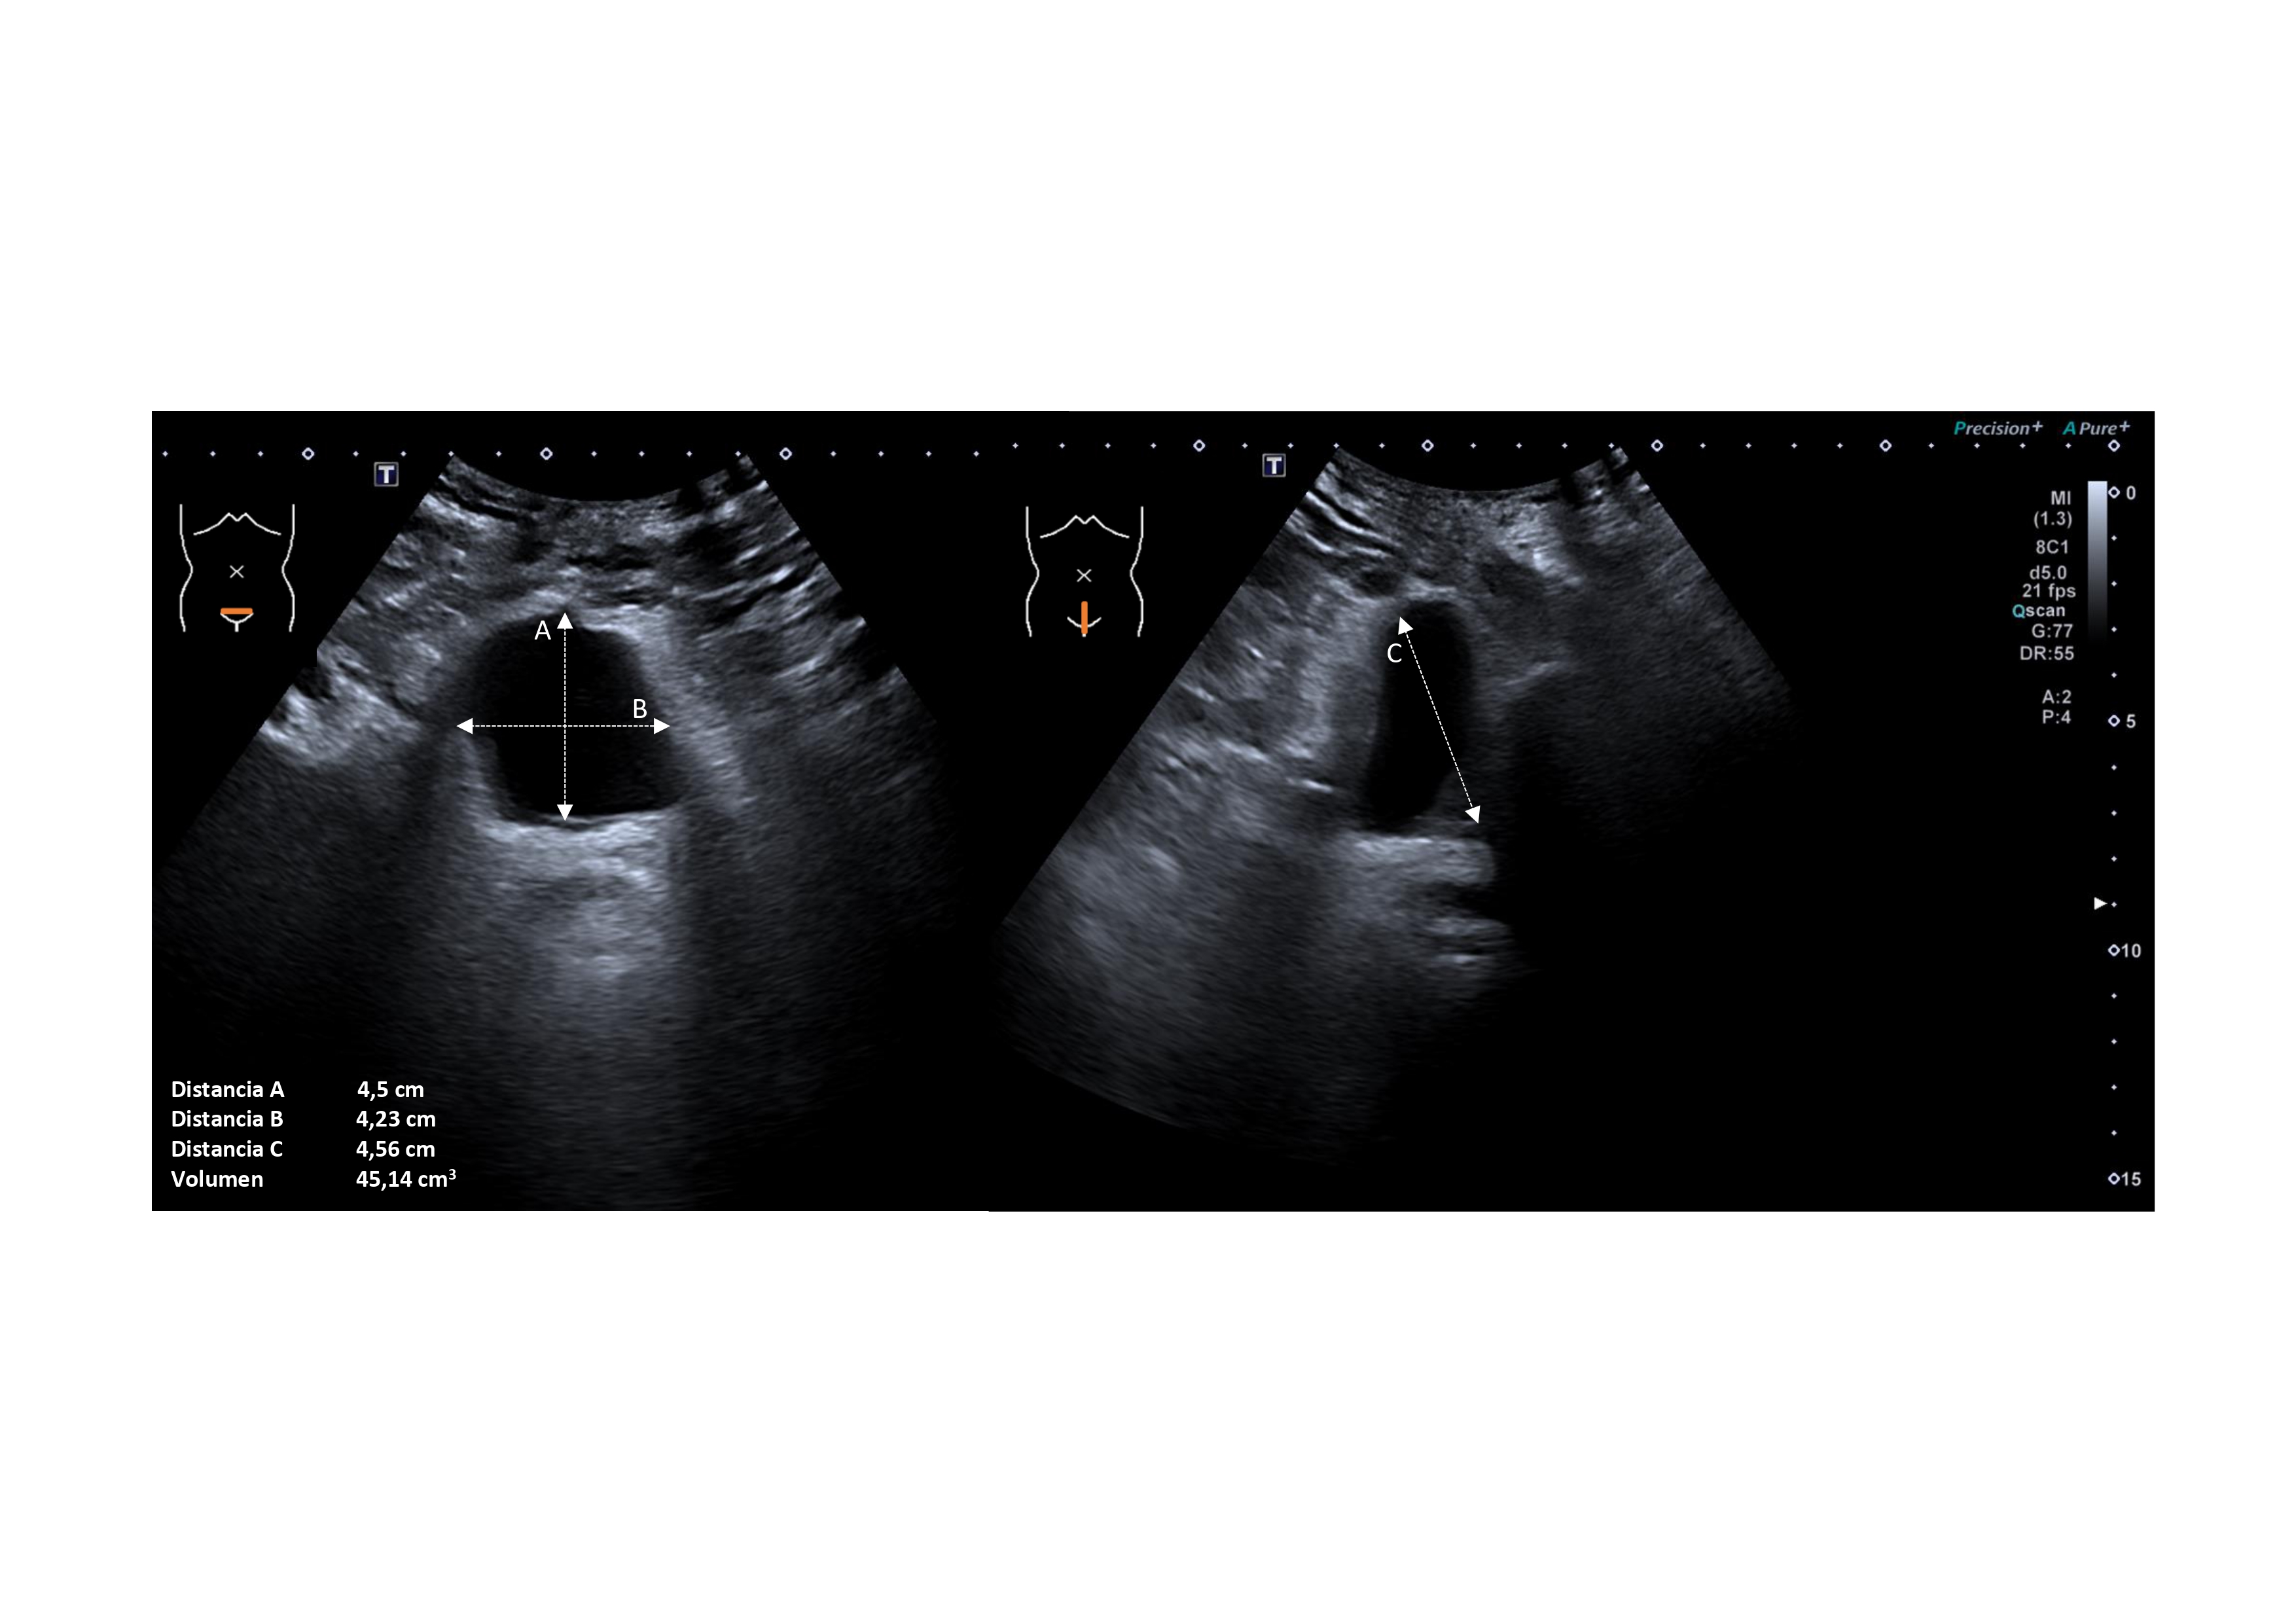

Se consultó con Urología, quienes recomiendan completar estudio por circuito habitual por encontrarse libre de recidiva. Desde Radiodiagnóstico se realiza nueva ecografía y sugieren realizar resonancia magnética (RM) ante la posibilidad de lesión intraabdominal herniada, y plantear posible biopsia en función de los resultados.

Dos meses después, la RM confirma lesión indeterminada nodular de 30 x 18 x 45 mm e intensa captación de contraste, compatible con tumor desmoide o hemangioma, aunque sin poder descartar una metástasis por antecedentes.